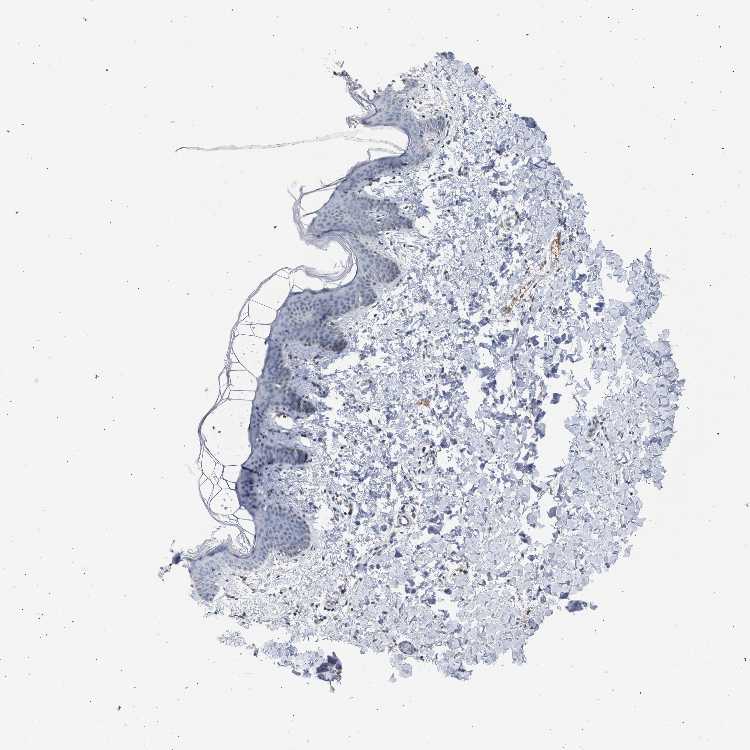

SKIN 1 - Antibody stainingi

Antibody staining in the annotated cell types in the current human tissue is reported as not detected, low, medium, or high, based on conventional immunohistochemistry profiling in selected tissues. This score is based on the combination of the staining intensity and fraction of stained cells.

Each image is clickable and will lead to virtual microscopy that enables deeper exploration of all samples and also displays staining intensity scores, fraction scores and subcellular localization as well as patient and tissue information for each sample.

Antibody HPA021061

Langerhans Not detected

Fibroblasts Not detected

Keratinocytes Not detected

Melanocytes Not detected

SKIN 2 - Antibody stainingi

Epidermal cells Low